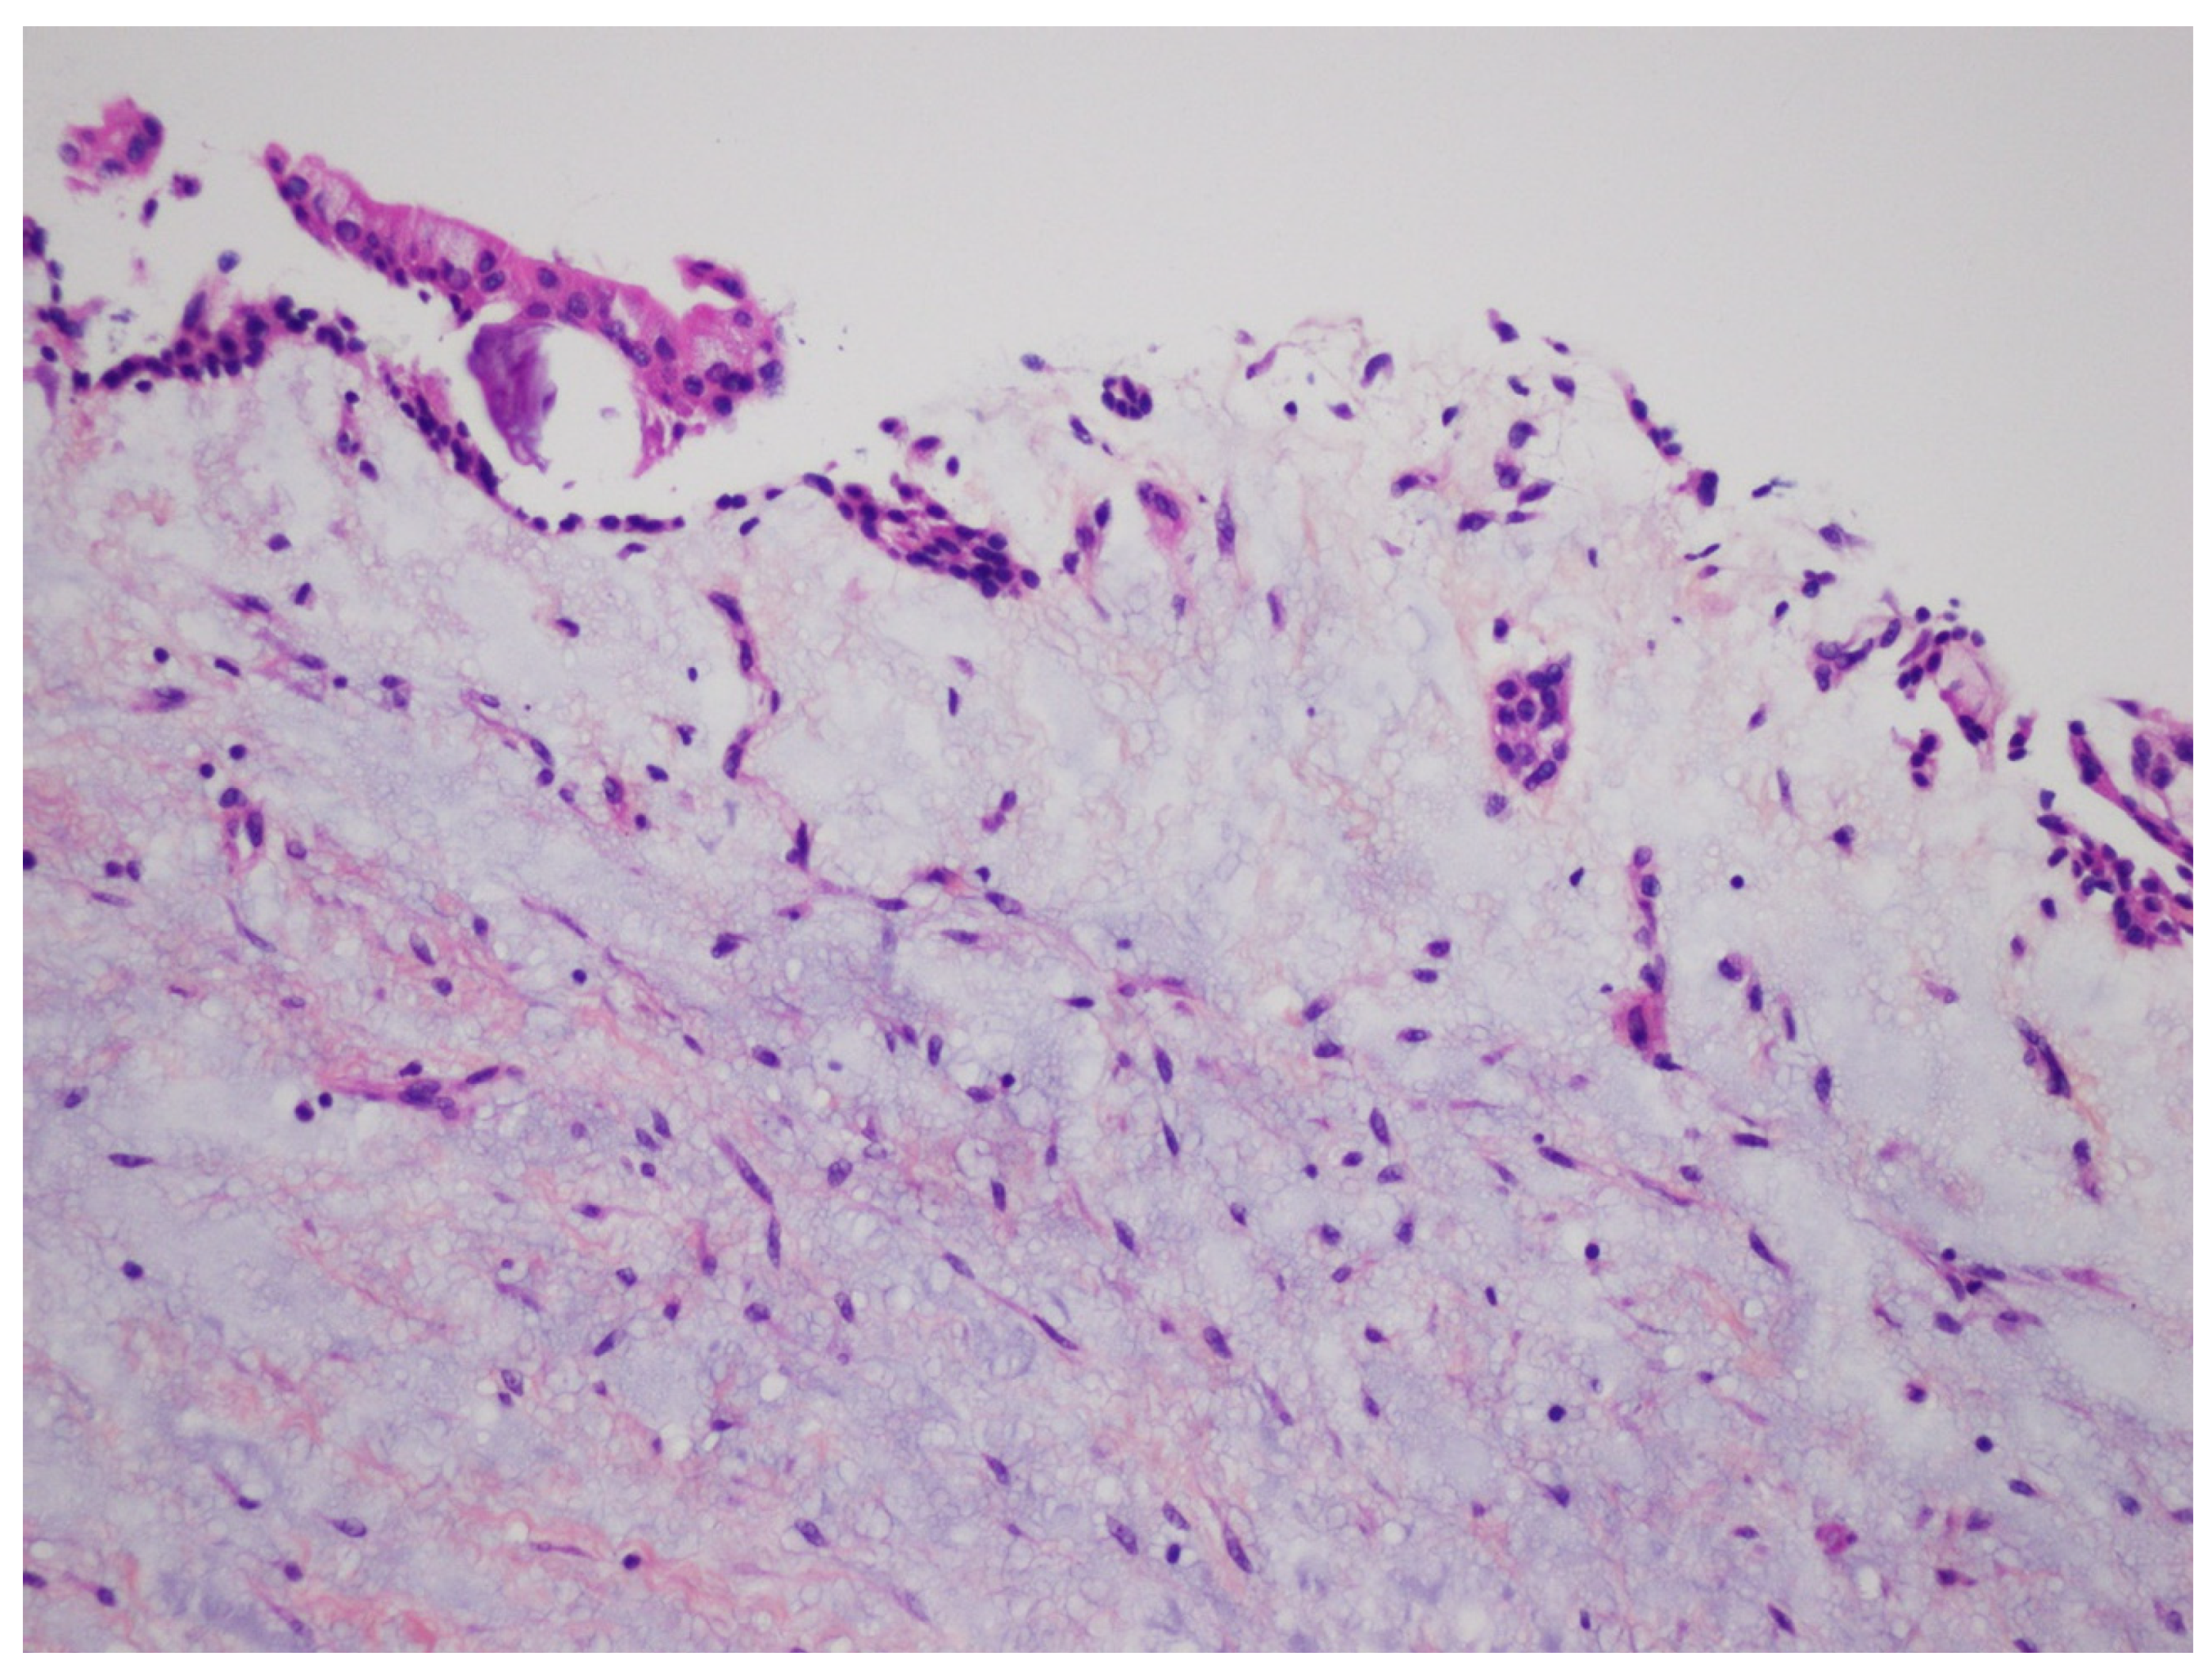

In the case of inflamed DC, histopathologic examination reveals a fibrous-connective tissue wall with a variable infiltration of chronic inflammatory cells and, on occasion, cholesterol clefts. The cyst is lined in part or entirely by non-keratinizing squamous epithelium, which shows varying amounts of hyperplasia with the development of elongated and interconnected rete ridges. These features may lead to a misdiagnosis of radicular cyst (Figure 15). Mucus cells or, rarely, ciliated columnar cells may be observed in the epithelial lining.

Figure 15.

Non-keratinized spongiotic squamous epithelium presenting hyperplastic rete ridges. The fibrous wall contains a lymphoplasmocytic infiltrate (H&E, ×10).